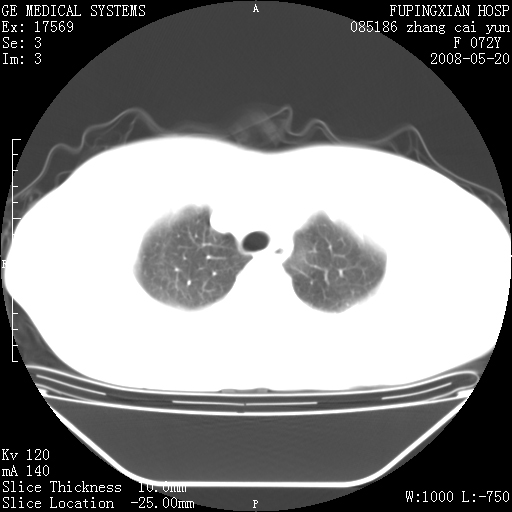

标题: CT13542:发热,咳嗽数日,经抗菌素治疗好转,请大家看排除 [打印本页]

标题: CT13542:发热,咳嗽数日,经抗菌素治疗好转,请大家看排除

右上叶支气管走行自然,未见明显管壁增厚等征像,另左主支气管起始部可见异常腔道向左侧延展左肺动脉干后方,与左下叶支气管相通,为左下叶支气管变异?

右肺上叶实变影,内见支气管充气征,右上叶支气管通畅,肺门区未见软组织密度影,抗炎治疗有效,考虑炎症,建议继续抗炎治疗复查。

右肺阻塞性肺炎  不除外支气管内膜结核

考虑为:右肺上叶感染性病变。建议:1)继续抗炎治疗后复查。2)必要时行纤支镜检查。